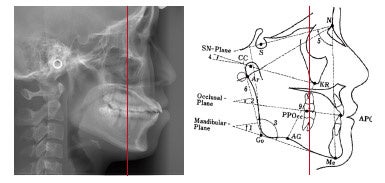

大阪矯正歯科グループ/クローバー歯科・矯正歯科が大切にしているのは、単に「歯並びの見た目をきれいにする」ことだけではありません。「正しい噛み合わせ」を構築することを同じくらい重要視しています。 具体的には、歯だけを見るのではなく、患者様の「骨格」から診断を行うアプローチを採用しています。頸椎に対する頭蓋の位置や、顎の関節のバランスを整えることから治療をスタートし、根本的な噛み合わせの土台を正すことで、結果として自然で美しい歯列へと導きます。